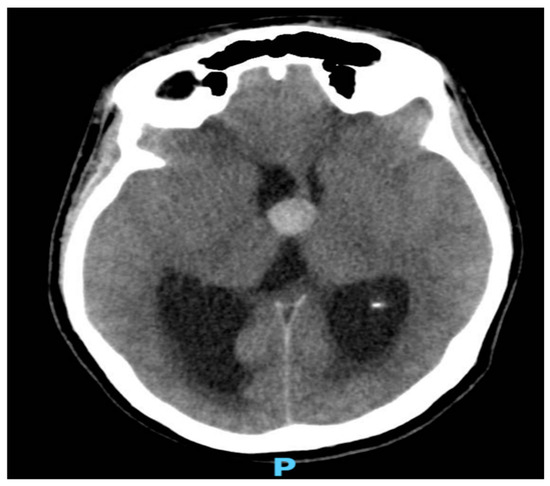

As shown in Figure 1 and Figure 2, neuroimaging with a head CT scan revealed a crucial finding: a colloid cyst situated at the roof of the third ventricle. This strategically located cyst was obstructing the normal flow of the cerebrospinal fluid (CSF), leading to obstructive hydrocephalus. Given the urgency of the situation, a prompt neurosurgical consultation was arranged.

Figure 2. A nonenhanced CT image of the brain showing dilated lateral ventricles more on the right side with surrounded periventricular hypo-density in keeping with CSF permeation.